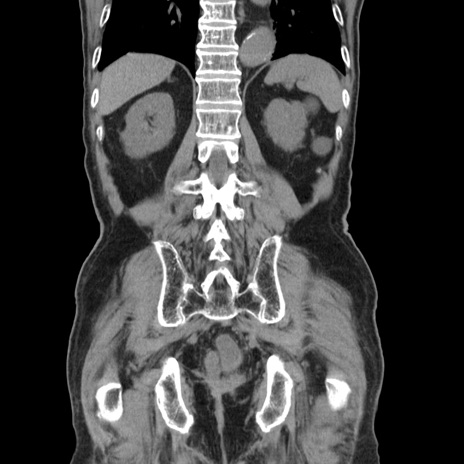

症例24(冠状断像)

【症例】80歳代男性

【主訴】左側腹部痛、嘔吐

【現病歴】本日早朝より左腹部に痛みあり。昼頃嘔吐認めたため、救急要請。

【既往歴】直腸癌(Mile手術)、胆摘

【身体所見】意識清明、BT 35.9℃、BP 221/93mmHg、SpO2 97%(RA) 、腹部:左ストーマ周囲に限局性の腹部膨隆あり。 膨隆部自発痛・圧痛あり・軟。

【データ】WBC 7700、CRP 0.09